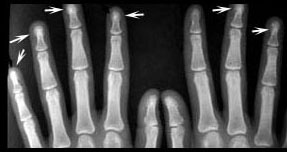

Acute polyarthritis is a common presenting symptom of sarcoidosis, but these patients do not have radiologic abnormalities. Visible bone lesions are associated with chronic disease and are rare unless the patient has skin lesions. The hands and feet are sites of lesions much more often than any other bone. The distal and middle phalanges are most often involved. The lesions are often few and inconspicuous, but rarely chronic disease leads to more severe and even destructive disease. Destructive granulomatous lesions can also occur in the facial bones and involve adjacent structures such as the paranasal sinuses, lacrimal glands, and optic nerve.

Focal osteolytic lesions in the fingers are the most common abnormality. The lesions in this patient are larger than usual.

Focal sclerosis (arrows) of distal phalanges is an unusual and nonspecific manifestation of sarcoidosis.